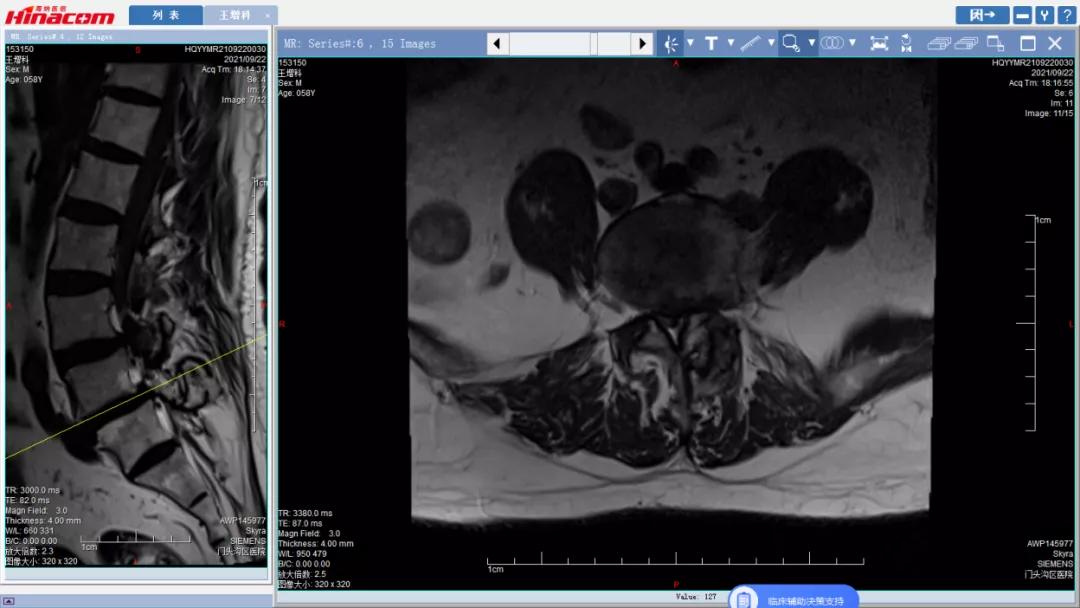

腰45椎管水平面--术前MRI

正常腰椎管水平面--术前MRI